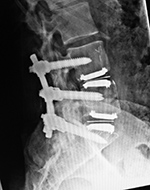

Metal-on-polyethylene total disk replacement at L4-5 and L5-S1 |

47 year-old man |

| Lumbar spine fusion and metal-on-polyethylene disk replacement at L4-5 and L5-S1 |

| 31 year-old man with chronic low back pain. In addition to the total disk replacements at L4-5 and L5-S1 there is also a laminectomy from L4 to S1 with posterolateral bony fusion masses and pedicle screws with connecting rods on each side. |